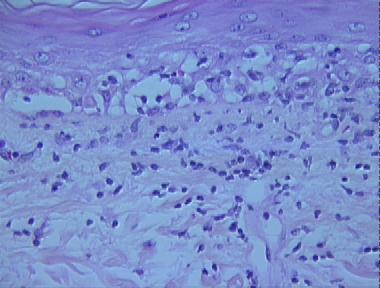

early lupus erythematosus

Histologic Features

- A basket-weave cornified layer

- Extensive vacuolar alteration of the basal layer

- A smudged thickened basement membrane

- A patchy lichenoid infiltrate of lymphocytes and histiocytes at the dermo-epidermal junction with a few neutrophils and nuclear dust

- Scattered necrotic keratinocytes in the basal layer and papillary dermis

- Extravasated blood cells in the papillary dermis

- Dilated blood vessels in the upper dermis

- A superficial and deep perivascular and periadnexal infiltrate consisting mostly of lymphocytes